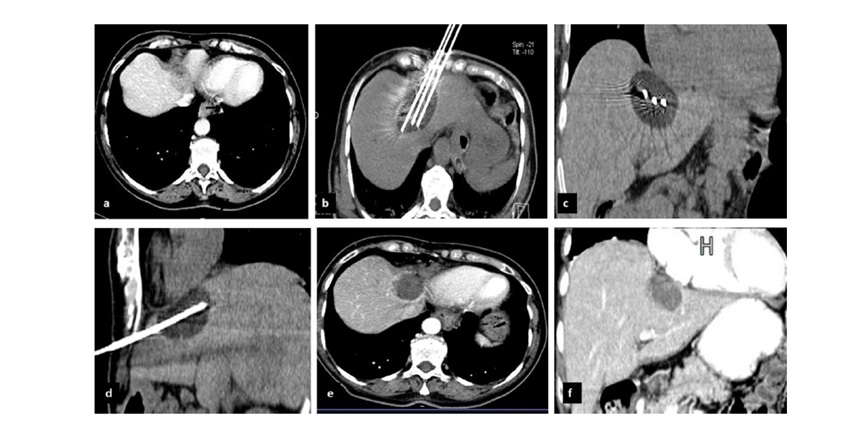

( a ) 軸向 MRI 和 ( b ) 軸向 CT 顯示肝S8段有一個(gè)16mm的病灶,鄰近肝緣。( c )冷凍消融期間CT顯示放置了2個(gè)冷凍探針,低密度冰球包圍病灶。(d)術(shù)后1個(gè)月隨訪 CT顯示冰球?qū)?yīng)的壞死區(qū)域,未見復(fù)發(fā)。(e)術(shù)后6個(gè)月的CT,壞死區(qū)域縮小,未見復(fù)發(fā)。(f)與基線影像(g)相比,12個(gè)月后的FDG-PET/CT顯示未見FDG攝取。

62歲女性,肝轉(zhuǎn)移(卵巢癌)腫瘤的完全消融病例(a)軸向CT顯示病變位置毗鄰心臟和上腔靜脈(黑色箭頭)。(b)術(shù)中軸向CT掃描:使用三個(gè)冷凍探針。1個(gè)月后的軸向(e)和冠狀位(f)增強(qiáng)CT掃描顯示低密度區(qū)域,由于肉芽組織反應(yīng)引起的邊緣增強(qiáng)。